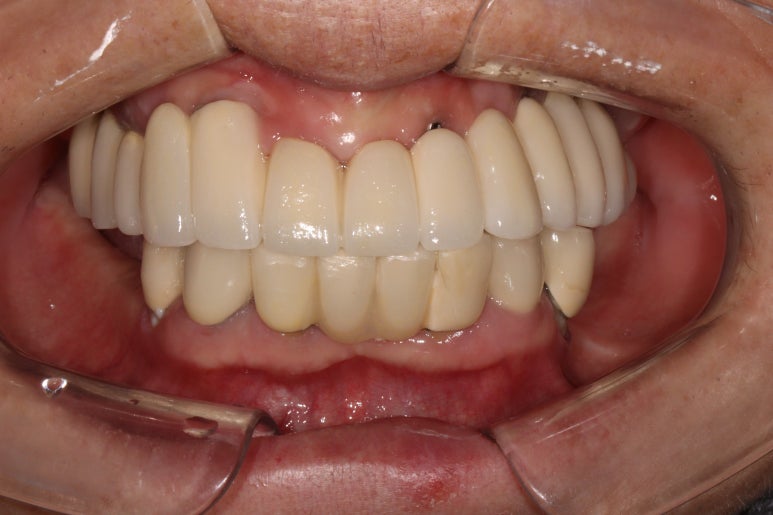

생각보다 임시치아보다 훨씬 매끈한 표면과 비슷한 색깔을 자랑하는 지르코니아 크라운입니다.

아마 어금니에 임플란트가 생긴건가? 싶으실거에요.

오스템 원가이드 네비게이션 임플란트 시스템을 이용하면, 정교하게 이상적인 위치에 임플란트를 심어낼 수 있어 자연스러운 임플란트 보철물을 제작하는데 많은 도움을 받을 수 있습니다!!

최종 완성된 보철물은 상당히 이상적인 형태를 갖고 있습니다.

이제 드디어 부분틀니를 쓰지 않아도 되는 ... 행복한 순간입니다.

치과용 파노라마 사진을 보면 뭔가 좌우 대칭으로 깔끔하게 완성된 아래턱 양쪽 어금니 임플란트를 보실 수 있어요!!

차이를 별로 못느끼실 수 있겠지만, 임플란트 보철물 완성 6개월 후 방문 때 구강내 사진입니다.

감사히도 환자분께서 상당히 깨끗하게 유지하고 계셔서, 잇몸에 염증하나 없이 너~무 보기 좋더라구요.